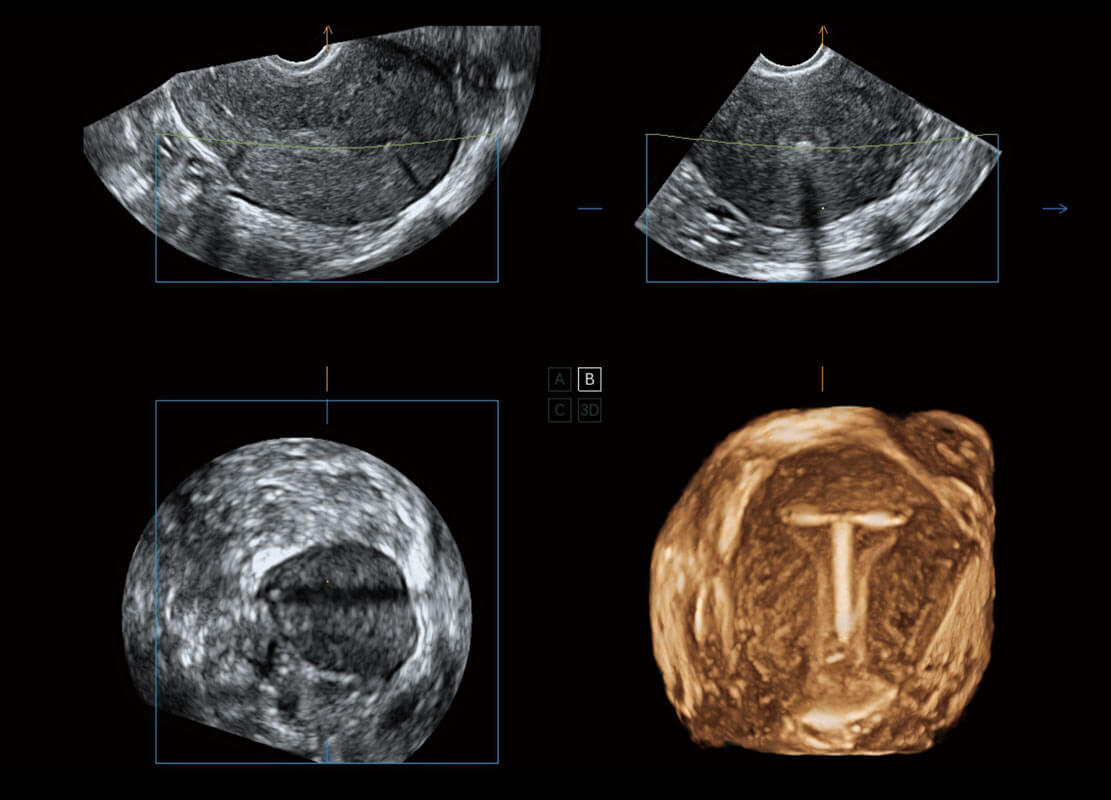

腔内三维-宫内节育器

P60为盆底超声检查提供应用方案,多种腔内及腹部容积探头提供从二维、三维到四维的优异图像品质,实时快速三维容积数据获取,专业的测量工具包等人性化设计,为超声医生诊断提供有力保障。

Lev.Hiat A-r: 16.33 cm2

Lev.Hiat H-r: 53.70 mm

Lev.Hiat W-r: 43.96 mm

Lt-LUG-r: 24.16 mm

Rt-LUG-r: 19.94 mm

能够简化盆底检查的操作流程,可在二维模式及三维成像模式下实现一键自动提取出标准切面、自动识别当前切面、自动测量,提升盆底检查的高效性,同时也能让青年医生快捷的获得准确的检查结果。